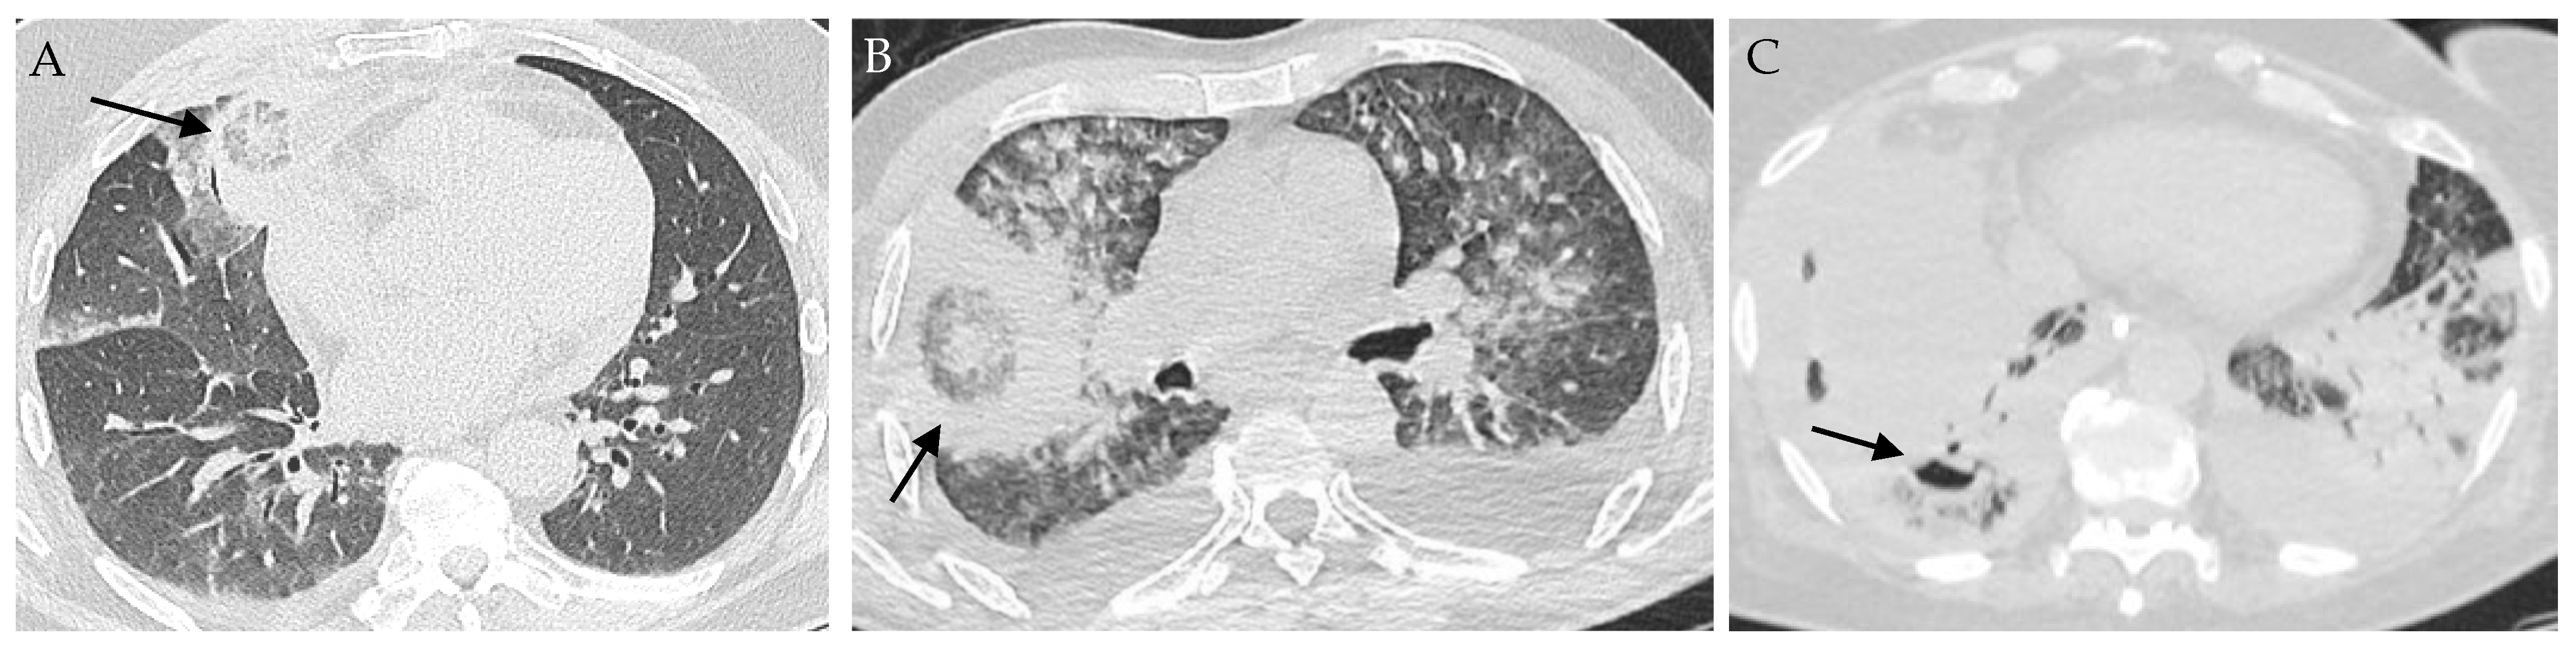

- Legouge, C.; Caillot, D.; Chretien, M.-L.; Lafon, I.; Ferrant, E.; Audia, S.; Pages, P.-B.; Roques, M.; Estivalet, L.; Martin, L.; et al. The Reversed Halo Sign: Pathognomonic Pattern of Pulmonary Mucormycosis in Leukemic Patients With Neutropenia? Clin. Infect. Dis. 2014, 58, 672–678. [Google Scholar] [CrossRef]

- Wahba, H.; Truong, M.T.; Lei, X.; Kontoyiannis, D.P.; Marom, E.M. Reversed Halo Sign in Invasive Pulmonary Fungal Infections. Clin. Infect. Dis. 2008, 46, 1733–1737. [Google Scholar] [CrossRef] [PubMed]

- Okubo, Y.; Ishiwatari, T.; Izumi, H.; Sato, F.; Aki, K.; Sasai, D.; Ando, T.; Shinozaki, M.; Natori, K.; Tochigi, N.; et al. Pathophysiological Implication of Reversed CT Halo Sign in Invasive Pulmonary Mucormycosis: A Rare Case Report. Diagn. Pathol. 2013, 8, 82. [Google Scholar] [CrossRef]

- Agrawal, R.; Yeldandi, A.; Savas, H.; Parekh, N.D.; Lombardi, P.J.; Hart, E.M. Pulmonary Mucormycosis: Risk Factors, Radiologic Findings, and Pathologic Correlation. Radiographics 2020, 40, 656–666. [Google Scholar] [CrossRef] [PubMed]

- Stanzani, M.; Sassi, C.; Lewis, R.E.; Tolomelli, G.; Bazzocchi, A.; Cavo, M.; Vianelli, N.; Battista, G. High Resolution Computed Tomography Angiography Improves the Radiographic Diagnosis of Invasive Mold Disease in Patients with Hematological Malignancies. Clin. Infect. Dis. 2015, 60, 1603–1610. [Google Scholar] [CrossRef] [PubMed]

- Jung, J.; My, K.; Hj, L.; Ys, P.; So, L.; Sh, C.; Ys, K.; Jh, W.; Sh, K. Comparison of Computed Tomographic Findings in Pulmonary Mucormycosis and Invasive Pulmonary Aspergillosis. Available online: https://pubmed.ncbi.nlm.nih.gov/25882362/ (accessed on 10 November 2022).